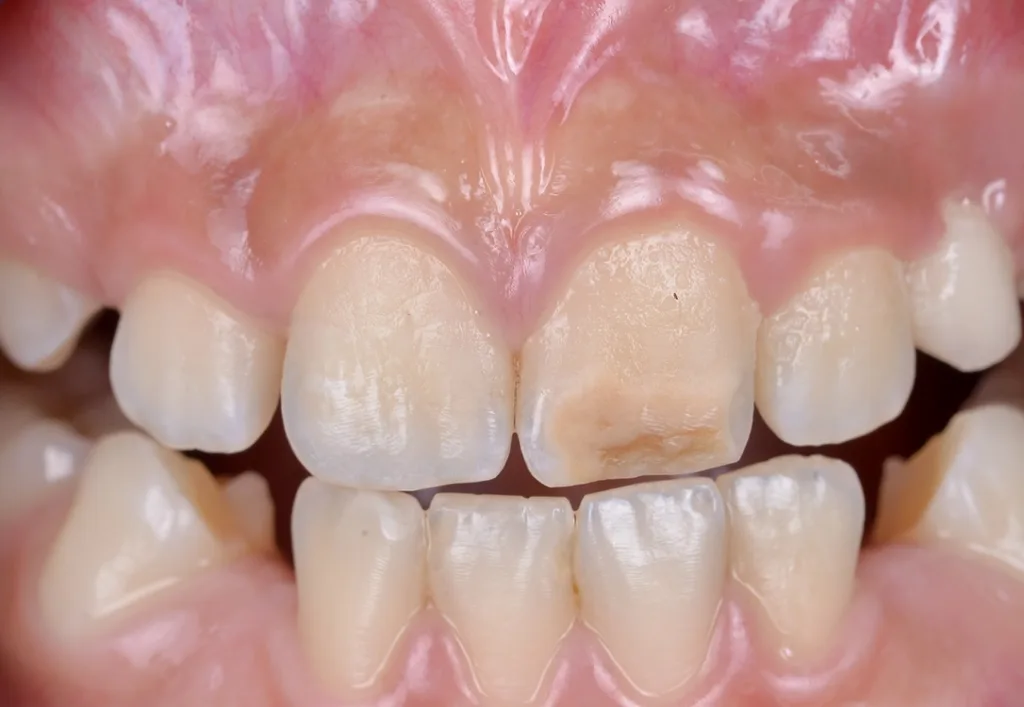

MIH-Läsionen an den Frontzähnen manifestieren sich häufig als klar abgegrenzte Opazitäten, deren Farbpalette von Weiß über Creme und Gelb bis hin zu Braun reicht. Diese farblichen Veränderungen sind ein wichtiger diagnostischer Hinweis auf die zugrundeliegende Strukturstörung des Zahnschmelzes. Besonders auffällig ist, dass die Intensität der Färbung mit dem Grad der Porosität und der strukturellen Beeinträchtigung des Schmelzes korreliert: Je dunkler und ausgeprägter die Opazität erscheint, desto höher der Restproteingehalt im Zahnschmelz, und desto höher ist das Risiko für posteruptive Substanzverluste, Frakturen und Hypersensitivitäten (Abb. 1). Die sorgfältige Beurteilung dieser visuellen Merkmale ist daher von zentraler Bedeutung für die Planung einer individuellen und effektiven Therapie, die sowohl funktionelle als auch ästhetische Aspekte berücksichtigt.